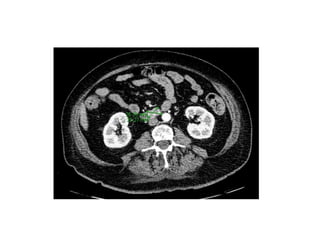

TAC TAP Septiembre

2016

Lesión 3ª porción

Duodeno 2-3cm

compatible con GIST.

Diseminación (-)

2014 Dolor Abdominal tipo Cólico Agosto2016: Se asocia Fatiga y Baja de Peso aprox.15 Kg y Melena. EDA: Septiembre ‘16 Lesión Subepitelial, ulcerado 2cm en 3ª porción duodeno. Bp: GIST Caso Clínico TAC TAP Septiembre 2016 Lesión 3ª porción Duodeno 2-3cm compatible con GIST. Diseminación (-) Laparotomía y Resección con Buena Evolución.